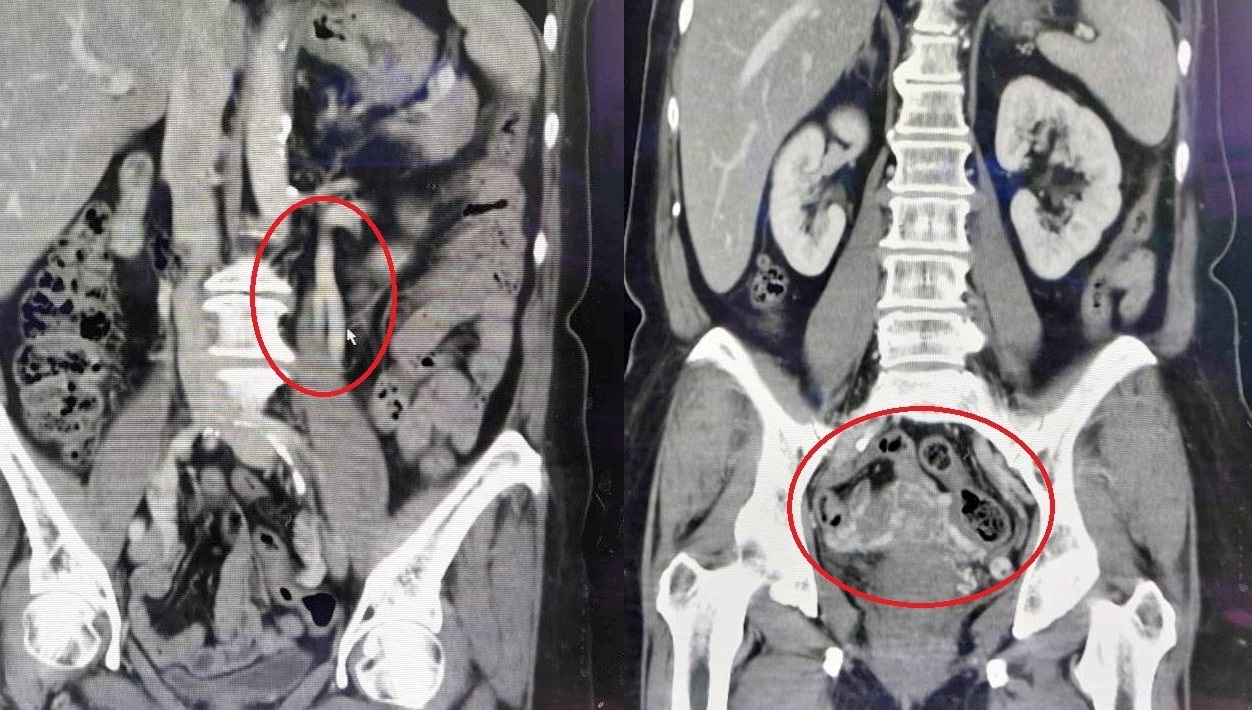

70歲王姓老婦長期遭受腰背痛和髖部疼痛的困擾,經過婦產科門診檢查,發現她的左側卵巢靜脈擴大,並且子宮及雙側卵巢旁有大量靜脈出現,導致骨盆腔鬱血症候群。這種情況主要發生在多次生產的女性身上,症狀包括持續的下腹部疼痛、腰背痛、經痛、性交疼痛和子宮異常出血等。治療方法包括微創靜脈栓塞手術,手術後恢復良好,症狀得到顯著改善。